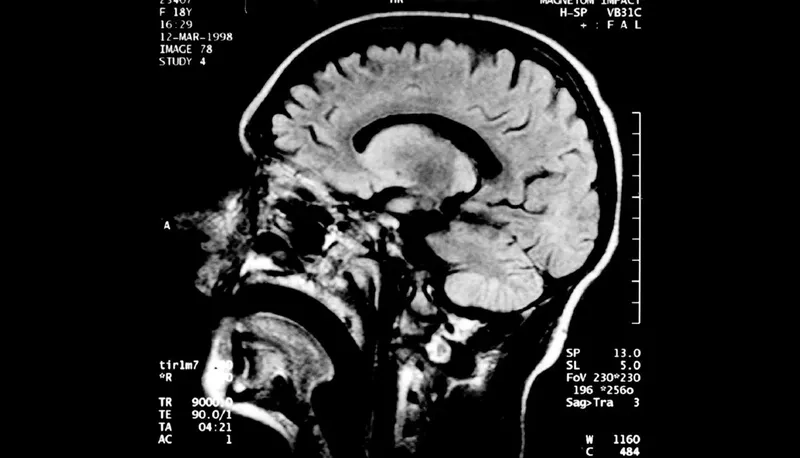

Recognizing Creutzfeldt Jakob disease symptoms

• Early symptoms include rapidly worsening memory problems, personality changes like apathy or irritability, and difficulties with balance, coordination, and walking.

• As the disease progresses, individuals may experience involuntary muscle jerks (myoclonus), blindness, weakness of the limbs, and severe mental impairment.

• The rapid decline in cognitive function and mobility is a hallmark sign, often leading to a complete loss of awareness and movement within a year.